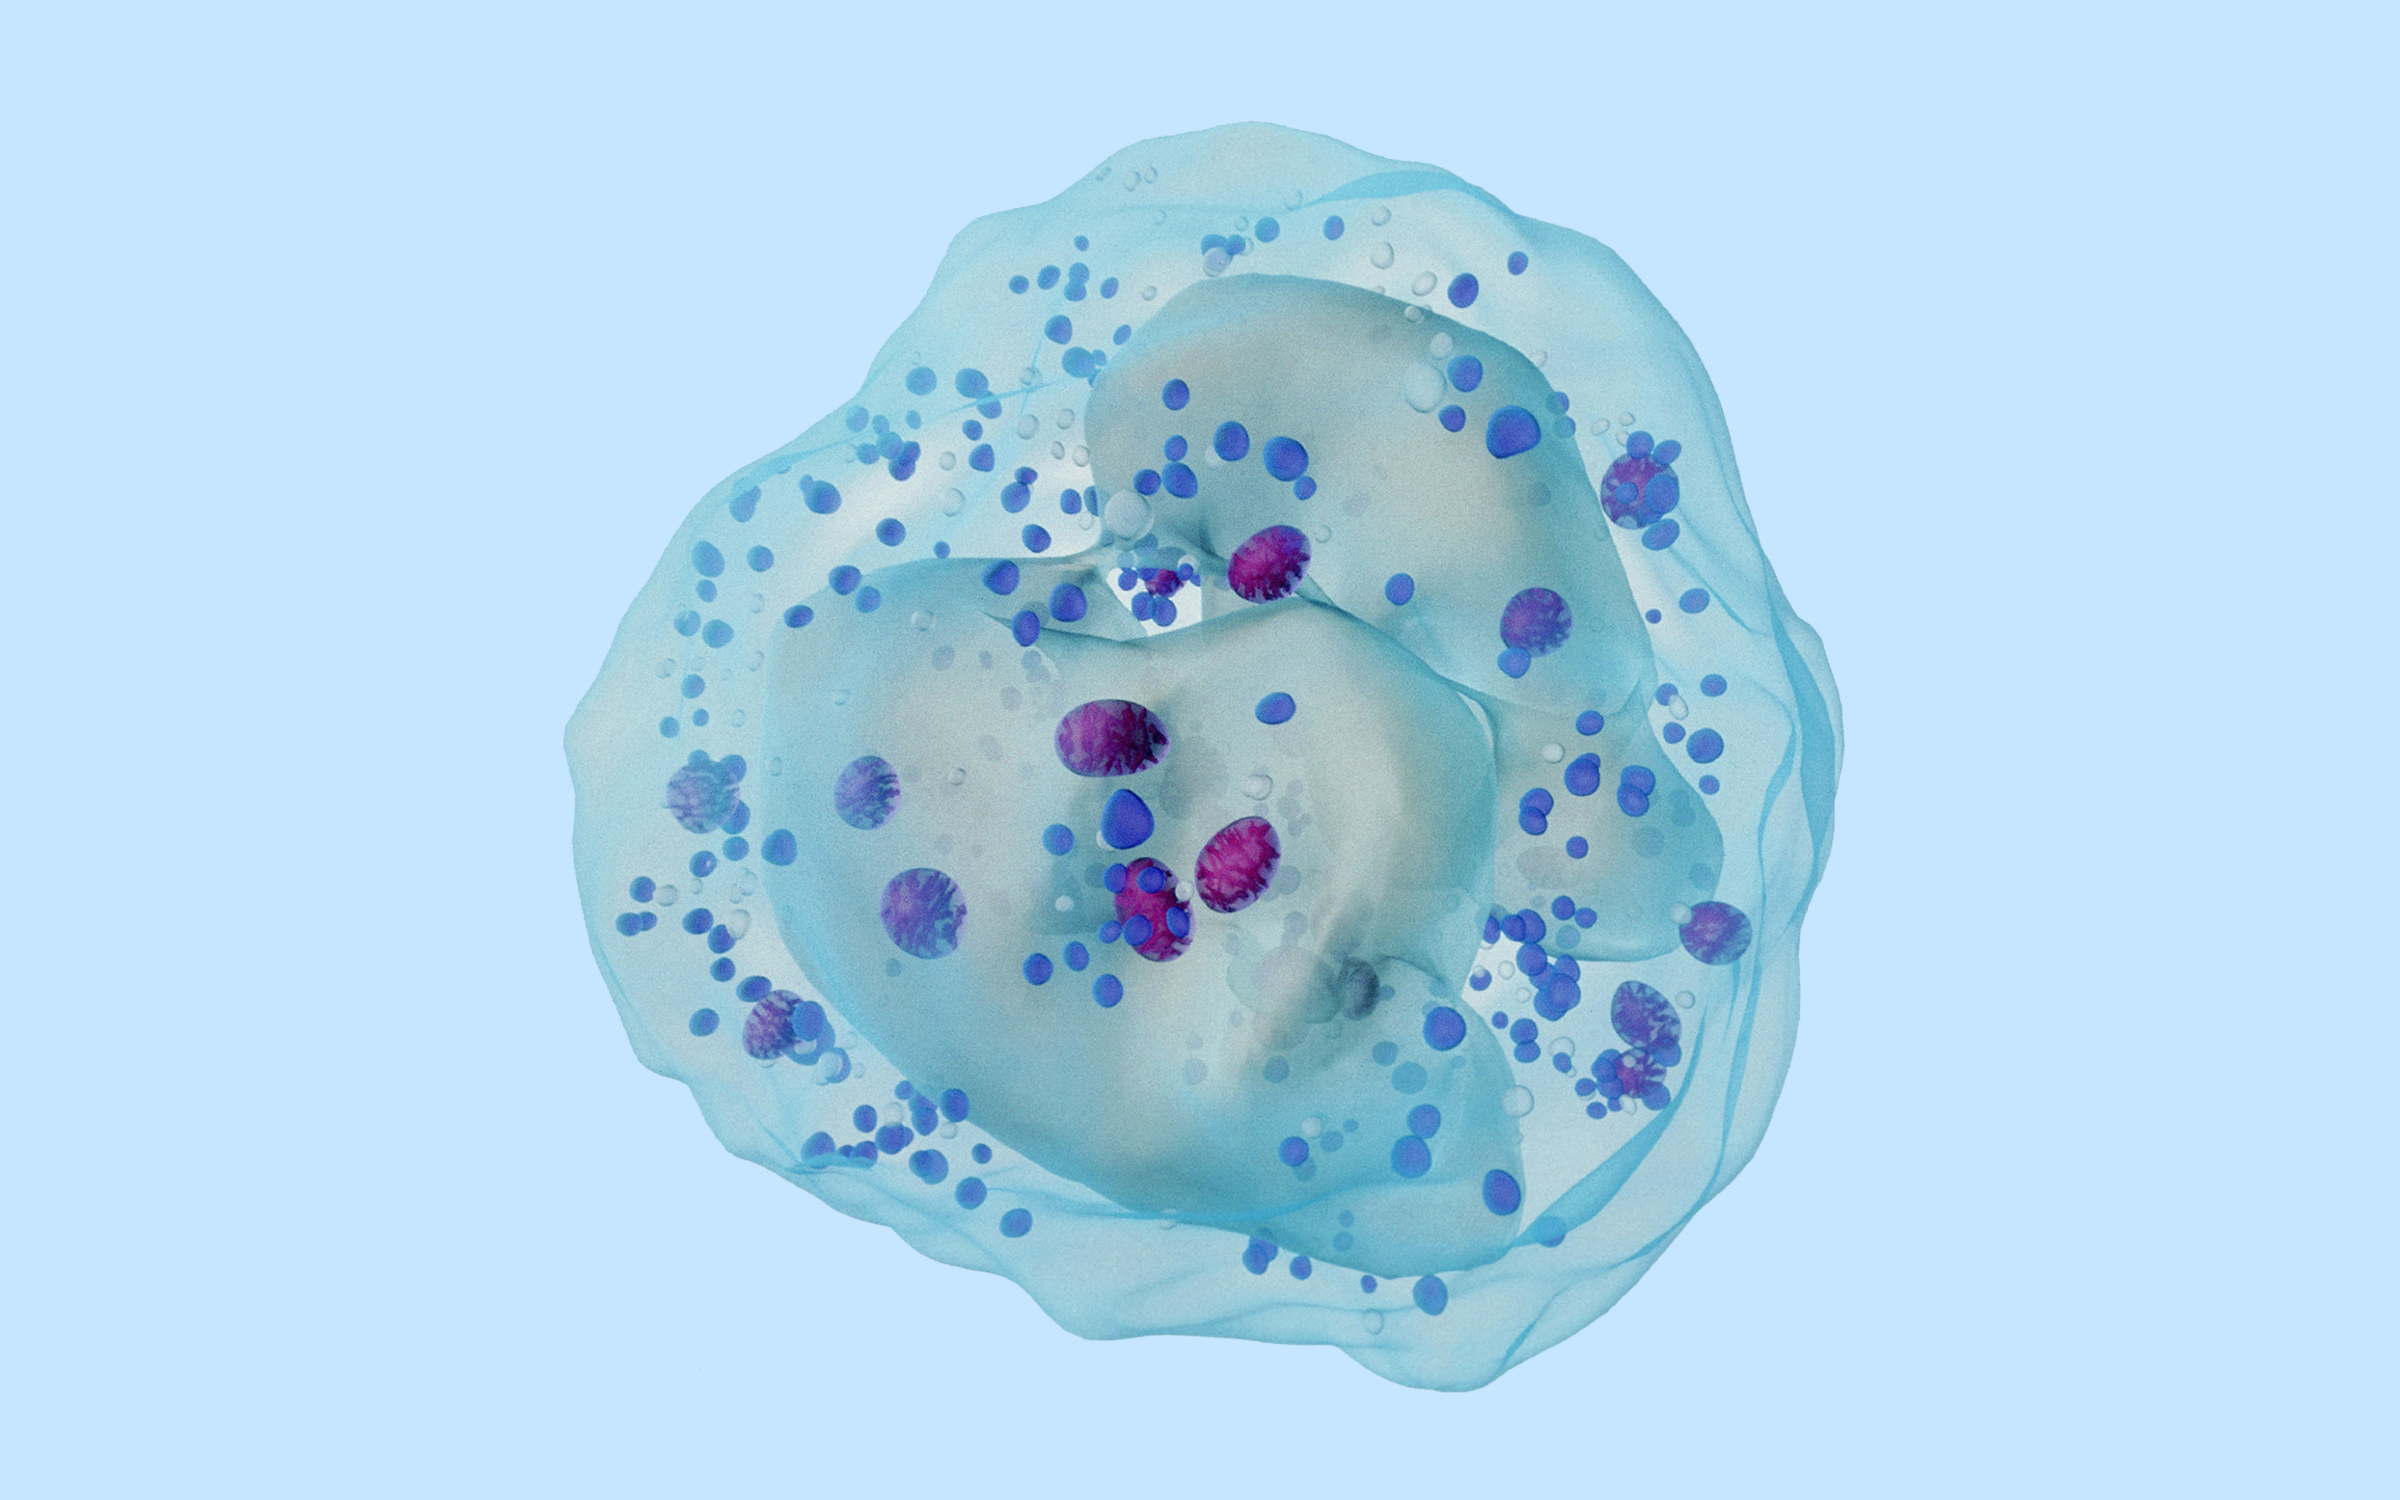

招募非霍奇金细胞淋巴瘤患者 | 全人源抗CD137单链抗体Fc融合蛋白注射液

项目用药:DF003注射液

一项在晚期恶性实体瘤或非霍奇金淋巴瘤受试者中评价DF003注射液单药治疗的安全性、耐受性、初步有效性及药代动力学特征的多中心Ia期临床研究